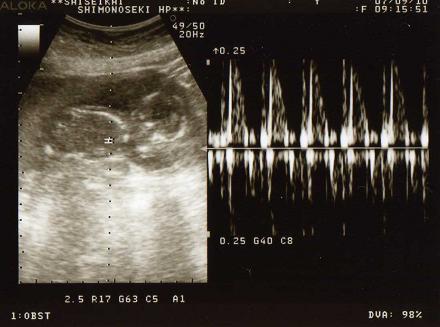

2週間ぶりの検診で

ドキドキしてたけど、何事もなく終了。

ベビの大きさを聞くのは忘れちゃったけど、順調に育ってはいるみたい~

頭の大きさが3.5cmだって

全長を考えたら、15cm位は行ってるかなぁ?足伸ばした状態でね。

次の検診は3週間後の10月1日です

性別、そろそろ解るかなぁ~~(´ ▽`).。o